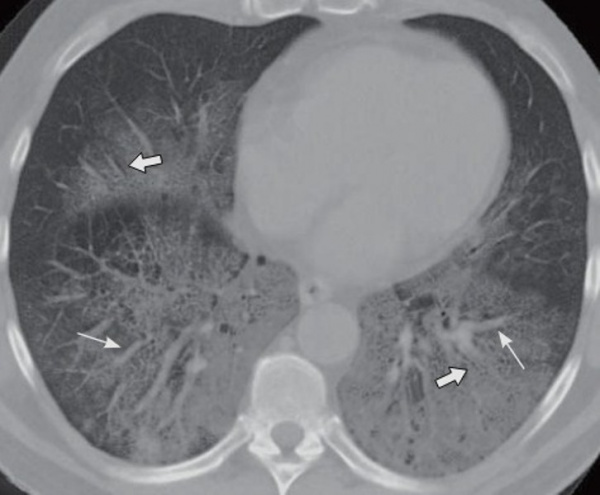

Повреждение легких от электронных сигарет и вейпинга на КТ напоминает пневмонию. EVALI определяется по «матовым стеклам» (очаги инфильтрации и уплотнения воздушной легочной ткани), локализованным преимущественно вокруг бронхов. Иногда при этом также наблюдается консолидация и симптом обратного гало. Чаще всего поражены субплевральные и нижнедолевые отделы легких — симметрично и с обеих сторон.*

- КТ грудной клетки. Рентгенологическое обследование выявляется двустороннее сегментарное или долевое снижение пневматизации легочной ткани (симптом «матового стекла»), утолщение междольковых перегородок (симптом «булыжной мостовой»). В поздних стадиях видны участки фиброза, уплотнение междолевой плевры.